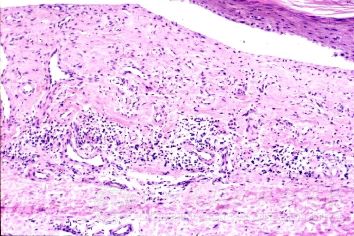

北京京城皮肤医院指出,光敏性皮炎是由日光照射皮肤后,通过光毒性作用或光过敏性反应而引起的。光敏性皮炎又称日光疹。表现为局部的发红发痒,另患者十分的痛苦。